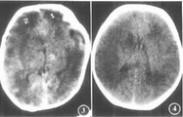

新生兒缺氧缺血性腦病癥狀

• 新生兒缺氧缺血性腦病

628健康網(wǎng)為您分享有關(guān)新生兒缺氧缺血性腦病的癥狀,新生兒缺氧缺血性腦病的治療方法,新生兒缺氧缺血性腦病的預(yù)防知識...